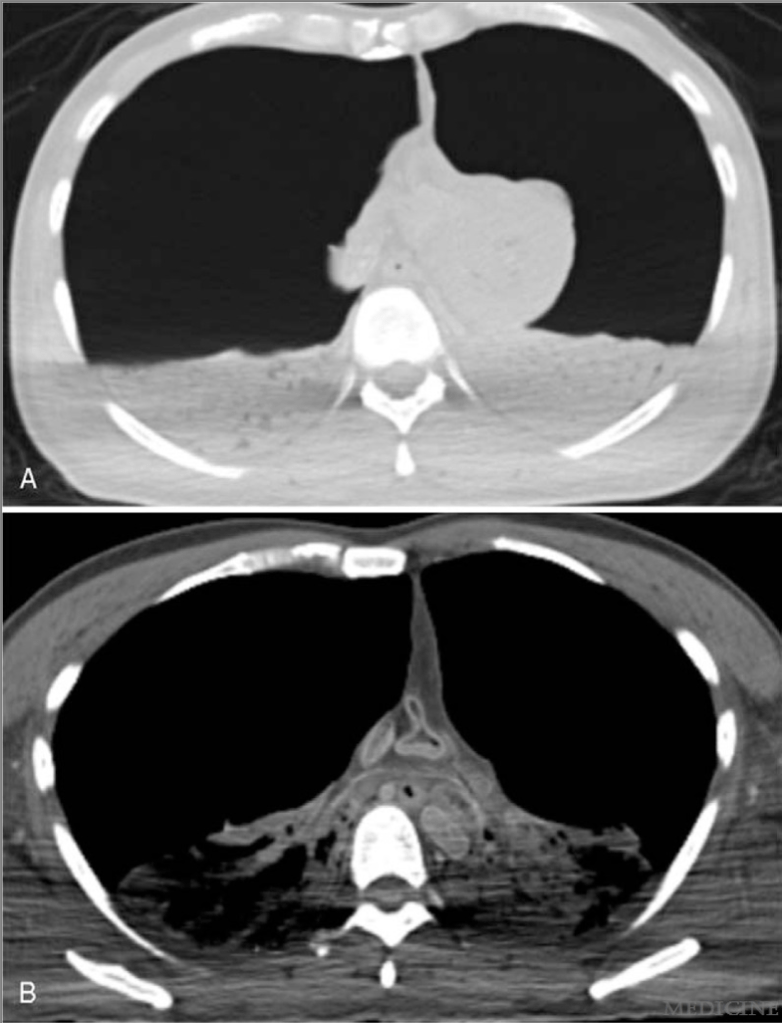

The body was frozen after death and then thawed before being subject to post-mortem computed tomography (PMCT), some 207 hours after death. The CT images demonstrate dramatic collapse and compression of both lungs as well as severe compression in the upper mediastinum. The trachea appears to be only mildly deviated because of bilateral tension, so this important sign in unilateral tension pneumothorax would not have been apparent on resuscitation.